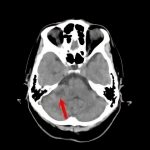

断層撮影

手術前1